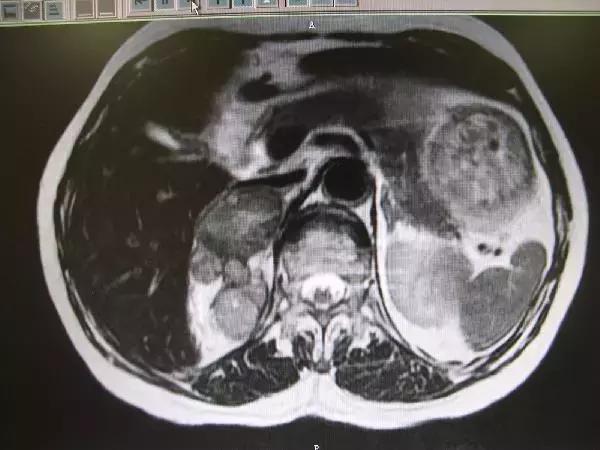

我们把查体时行影像学检查而发现的肾上腺肿物称为肾上腺意外瘤。由于影像学的进步,近年肾上腺意外瘤越来越多。因为瘤长在肾上腺上,而肾上腺又分泌多种激素,所以遇到肾上腺瘤首先我们应该了解:

一般来讲,肾上腺意外瘤中有80%是无功能性的,5%为亚临床库欣综合征,5%为嗜铬细胞瘤,1%为醛固酮瘤,小于5%为肾上腺皮质癌,2.5%有远处转移,其余的为神经节瘤、髓脂肪瘤或是良性的囊肿。不同功能的肾上腺瘤会对身体造成不同的影响,从而伴随不同的临床表现。